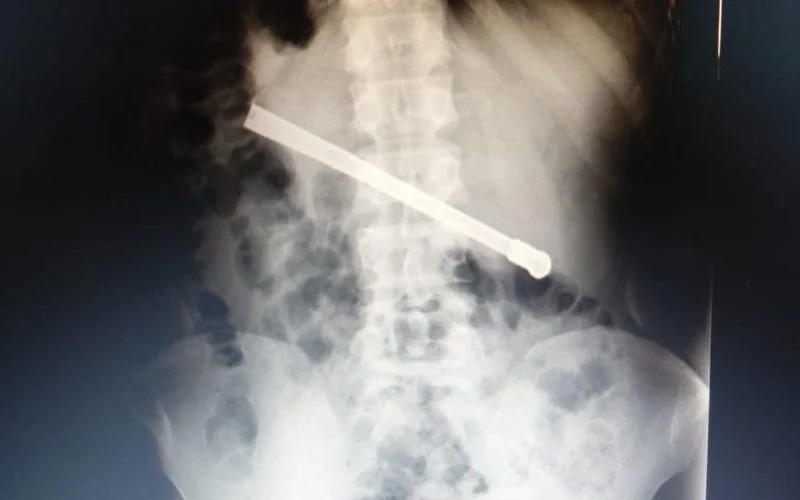

En la noche del domingo, un preso que se encuentra alojado en el Complejo Penitenciario Rosario solicitó atención médica de manera urgente debido a una fuerte dolencia estomacal. Es por ello que, con las medidas de seguridad pertinentes, fue trasladado al servicio médico para ser atendido. Al continuar con el malestar, le realizaron una placa radiográfica en la Unidad Penitenciaria ubicada en 27 de Febrero al 7800. En la misma pudieron determinar que había ingerido una bombilla de mate que quedó alojada transversalmente en la cavidad torácica.

En virtud de esto, el interno fue derivado al hospital Eva Perón para recibir una mejor atención, por lo que quedó internado para ser intervenido quirúrgicamente esta tarde. Tras culminar satisfactoriamente la operación y quedará en observación hasta volver al CPR.